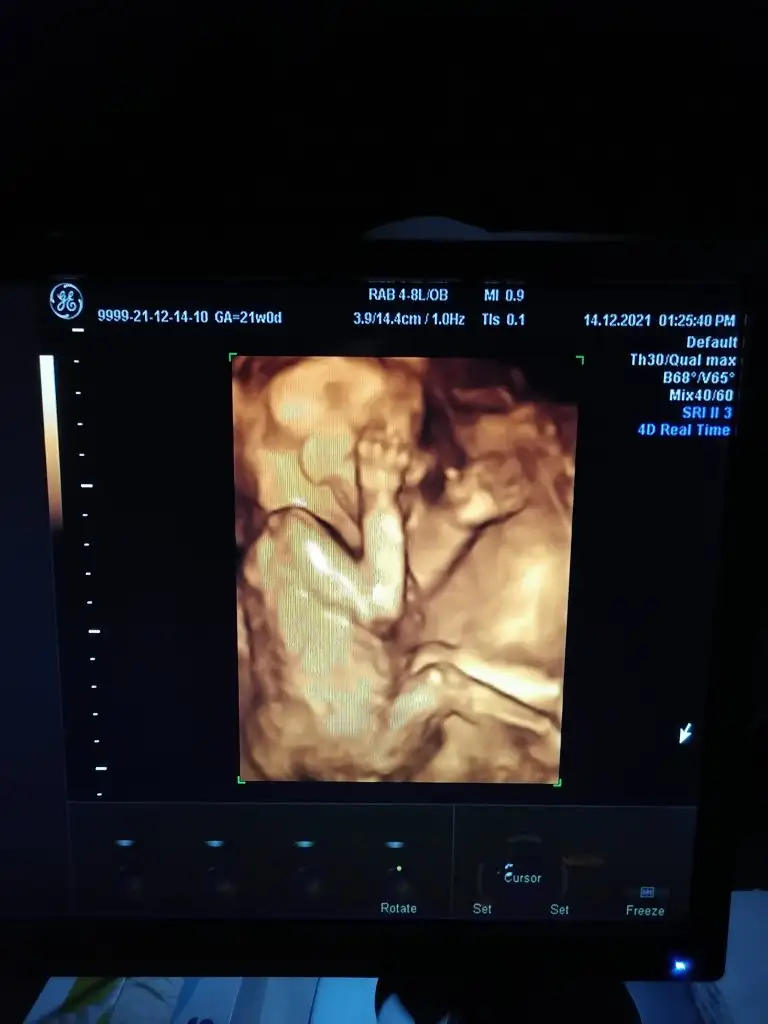

Teşekkür ederim destek mesajlarınıza, bir yandan çalışmak iyi geliyor kafam dağılıyor ama akşamları dayak yemiş gibi oluyoruz eşimle. İnanın bebeğin görüntülerinin keyfine varamadık. Öyle hareketli, öyle tatlı ki. Gün boyu benimle iletişimde olması kalbimi ısıtıyor. Sanki "Ben iyiyim anne, merak etme." der gibi.

Dünden beri çok rahatsızım okudum ama yazamadım . Senin için ve o tatlı bebişin için bol bol dua ediyorumGünaydın kızlar, Cuma günü detaylı ultrasonum vardı. Yazmak için kendime gelmeyi bekledim.

Bebeğin her şeyi normal, bir şeyi hariç. Kalpten çıkıp sağ kola giden bir damar var, yemek ve soluk borusunun önünden geçmesi gerekirken arkasından geçiyormuş. Bu teşhisin adı da "aberran sağ subklavyen arter" (ARSA)

Başta ne olacak sanki, bir damar sadece dedim ama durum öyle değilmiş. Buna özellikle bakarlarmış.

3 durumdan bahsettiler;

Bu durum normalin bir varyantı da olabilirmiş, yani belki bizlerde de var bilemiyoruz dediler. Ama Down sendromu veya Di George sendromu da olabilirmiş. Ben zaten fetal DNA yaptırmıştım. Temiz çıkmıştı. Doktorun yönlendirmesi ile düşük paketi yaptırmışım. Yani Down sendromuna bakılmıştı ama Di George bakılmamıştı.

Şimdi diyorlar ki damarın yanlış yerde olmasından başka anormallik görülmüyor, ne kalbinde, ne beyninde. Muhtemelen sağlıklıdır ama isterseniz geniş panel fetal DNA yaptırın. Ani bir kararla cumartesi sabah yeniden kan verdim. Onca masrafa şimdi de bu eklendi. Geri sayıma başladım. Sonuç bekliyorum.

Hadi para kazanılır, Allah güç, sağlık versin ama 2 kere fetal DNA yaptırdığıma mı sinirleneyim, çekeceğim strese mi yanayım yoksa genetik bozukluğu olmasa da bu damar yapısıyla yutkunma problemleri yaşayabilirmiş, buna mı üzüleyim. Çok rahatsızlık yaşarsa basit ameliyatı varmış. Doğumdan itibaren çocuk kardiyoloğu takipli olacakmış.